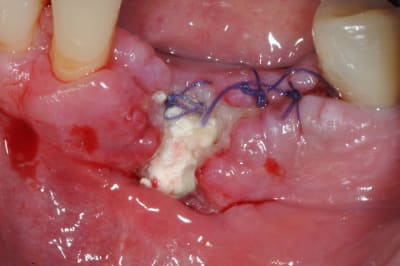

je sais pas si c'est un produit miracle, mais pour les sinus lift, c'est fantastique.

outre le fait de stabiliser un implant dans un sinus type SA4, pas de risque de voir partir le produit comme avec les granules de bioos et autres..

l'autre avantage est de ne pas avoir à mettre de membrane de recouvrement.

l'application type du VitalOs, avec le bone splitting.

le protocole tel qu'il est d'écrit voudrait que l'on applique d'abord une couche de vital os en palatin - laisser durcir - mettre l'implant puis mettre une dernière couche.

ici, j'ai mis l'implant- maintenu la membrane de Schneider en poussant avec l'embout sur celle ci et terminer l'injection du produit. c'est l'un des avantages de ce produit, il est livré avec deux embouts donc les deux solutions sont possibles pour une même seringue.